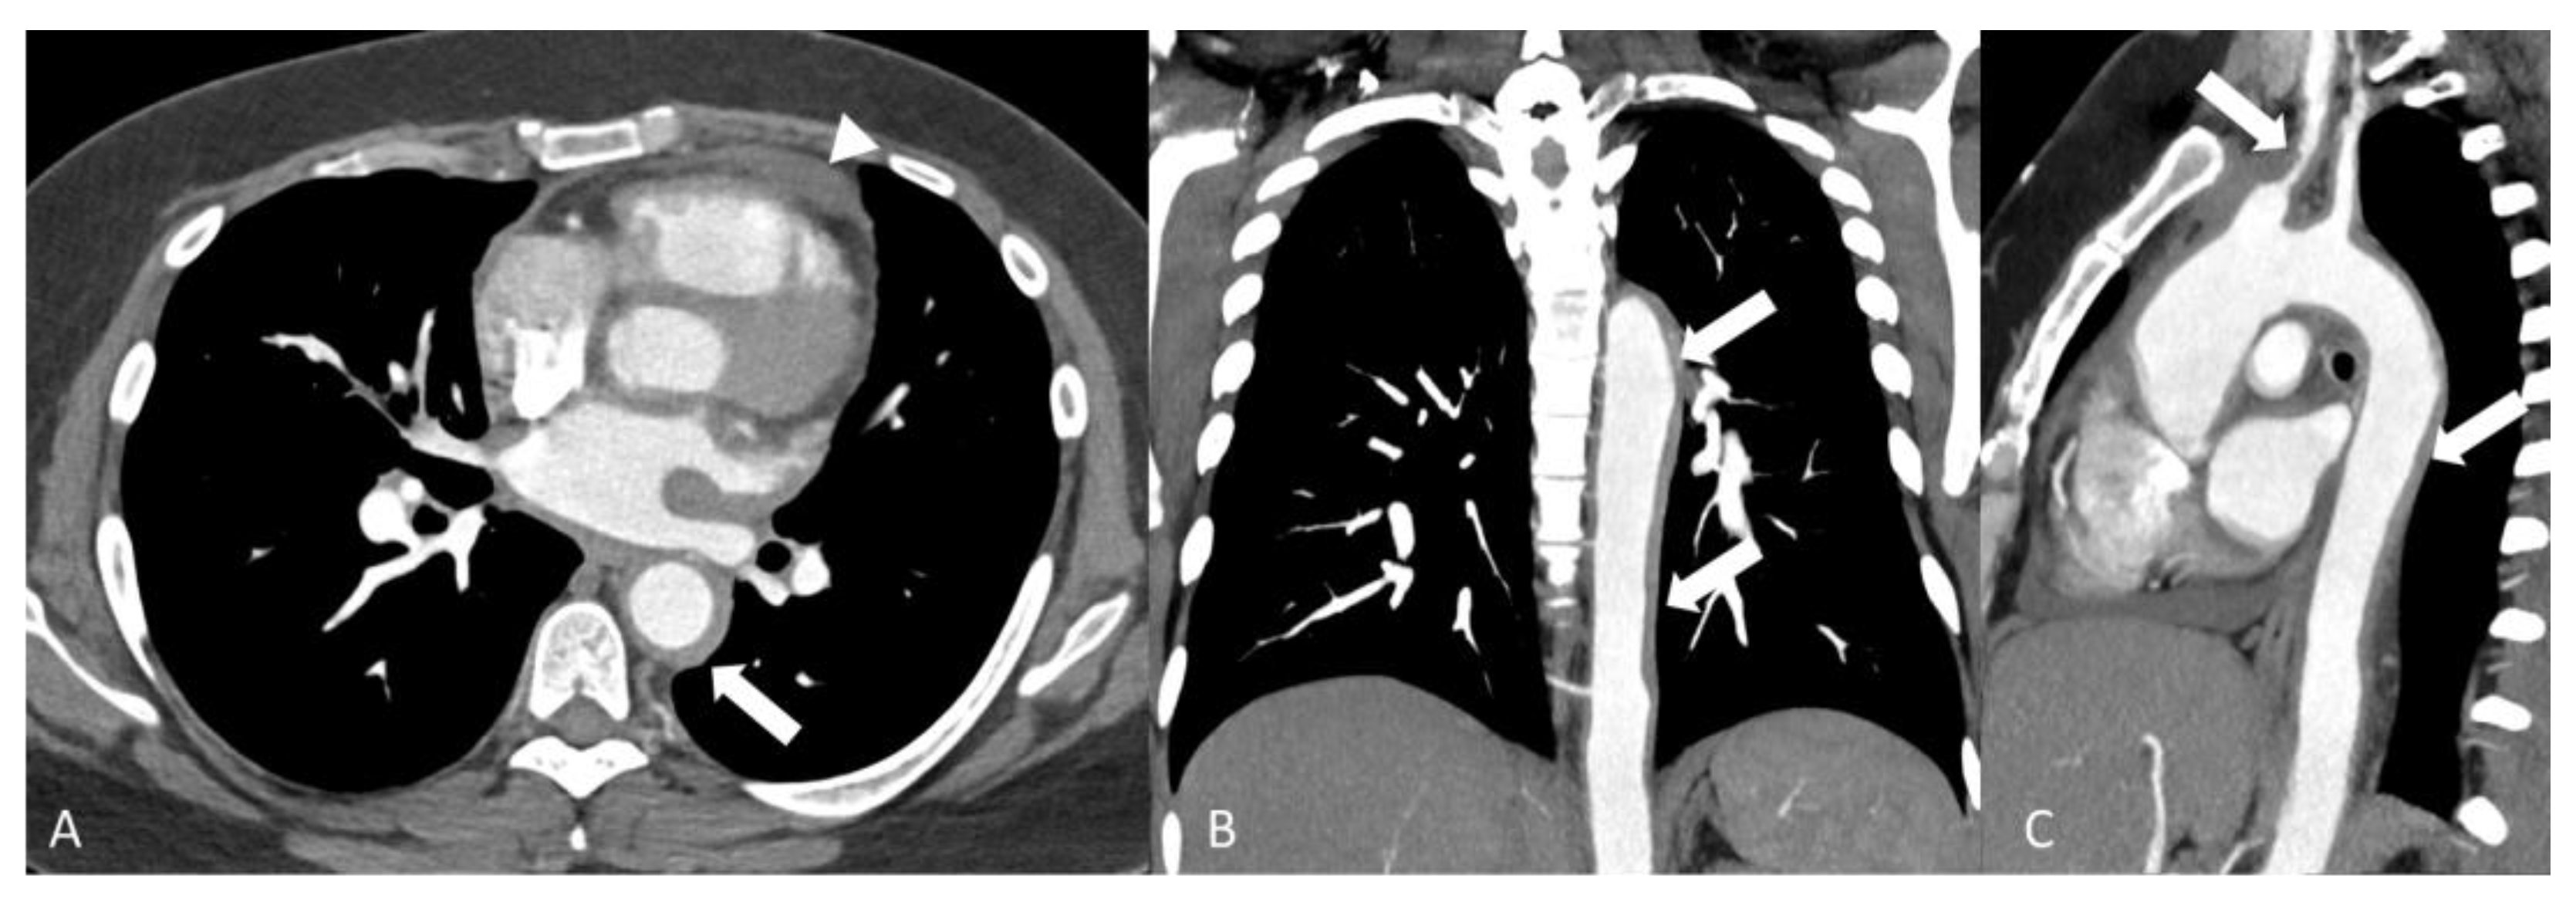

2.4.1. Behçet’s Disease